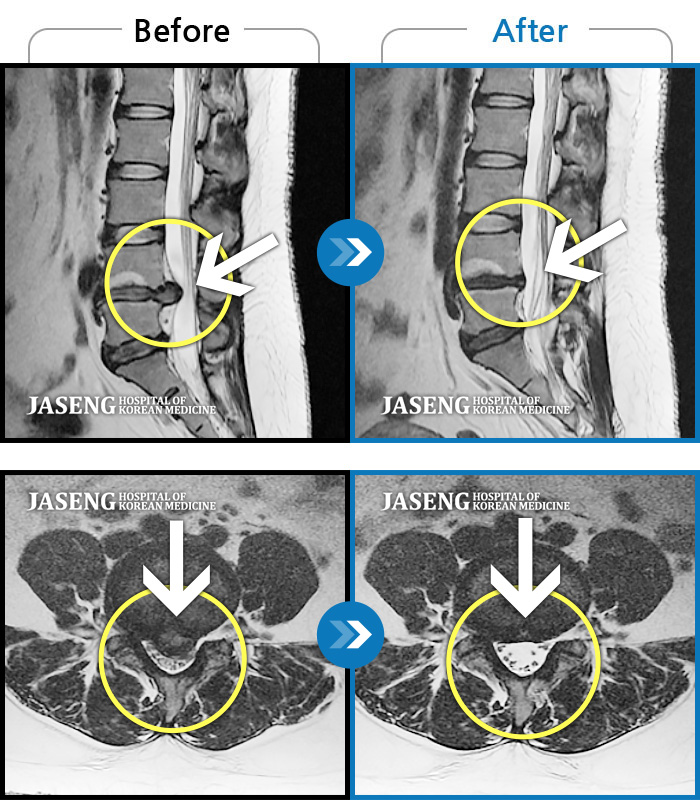

Before

After

환자에게 사전 동의를 받아 동일 조건에서 촬영되었습니다.

개인에 따라 치료 후 부작용이 발생할 수 있으니 의료진과 상담 후 치료를 진행하시기 바랍니다.

허리통증과 좌측 엉덩이에서 다리까지 방사통, 야간통

좌측 엉덩이부터 종아리까지 저림 및 통증